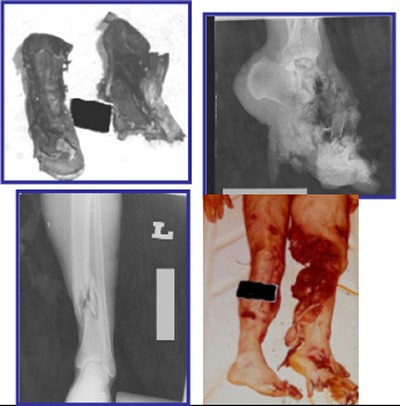

| An example of a typical pattern I mine injury. Two radiographs and corresponding photographs showing the traumatic amputation of the foot stepping on the mine (mine blast wound) and the contralateral long bone fracture (mine blast injury). The photograph of the boots was taken from the casualty. Caption courtesy of Drs. Justin Dodge and James Smirniotopoulos, photos and radiographs from the WDMET archive. |

- Pattern I results from standing on a buried blast mine. Victims sustain traumatic amputation of the lower limb and often injure the other lower limb or genitalia.